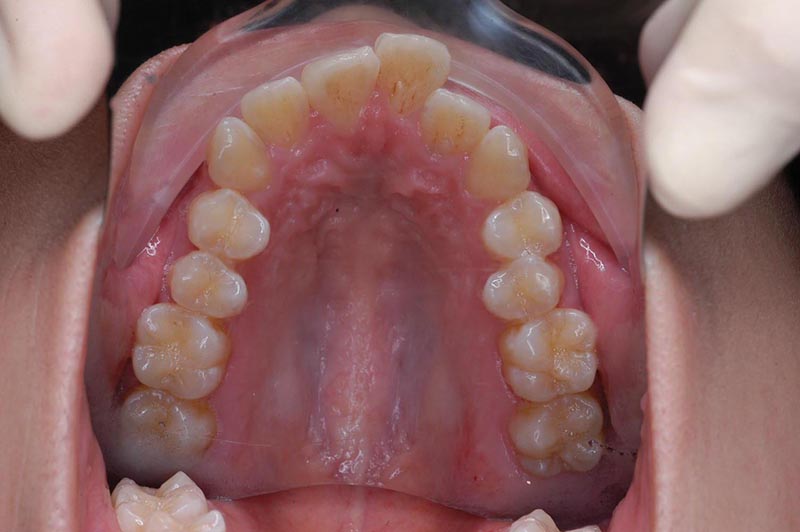

主訴 口が閉じづらい 診断名 アングルⅠ級上下顎前突症例

初診時年齢 19歳5ヵ月 性別 動的治療期間 26ヵ月

口腔内所見 大臼歯関係はⅠ級。顔面正中に対して上顎正中は一致しており、下顎正中は右側に偏位していた。上下顎前歯は大きく唇側傾斜し、overjetが7.8mmの上突咬合、両突歯列、叢生歯列弓であった。

セファロ所見 Sellaから下顎頭までの距離は短い。下顎枝、骨体部共に大きく下顎角はそれほど大きくはない。頭蓋底の前後的距離は短くなく、中顔面の奥行きもあるが、NasionからA点までの垂直的距離があるため、下顎はクロックワイズローテーションをしておりⅡ級傾向が認められた。上下顎前歯は唇側傾斜を呈していた。

パノラマ所見 上下顎左右側8は埋伏していた。